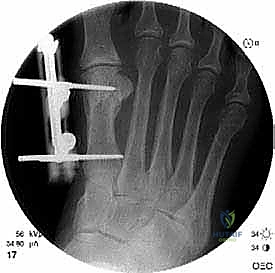

الخطوة الخامسة: التثبيت الداخلي القوي (Internal Fixation)

لضمان التئام العظم في وضعه الجديد والطويل، يجب تثبيته بقوة شديدة. يستخدم الدكتور هطيف أحدث الشرائح المعدنية التيتانيوم ذات الزاوية الثابتة (Locking Plates) والمسامير الدقيقة. هذا التثبيت القوي يمنع أي حركة بين العظام ويسمح ببدء العلاج الطبيعي في وقت مبكر.

الخطوة السادسة: الإغلاق التجميلي

بعد التأكد من الطول المثالي واستقرار التثبيت باستخدام الأشعة السينية في غرفة العمليات، يتم غسل الجرح بمضادات حيوية وإغلاق طبقات الأنسجة والجلد بخياطة تجميلية دقيقة لتقليل الندبات قدر الإمكان. يتم وضع ضمادة ضاغطة وداعمة للقدم.